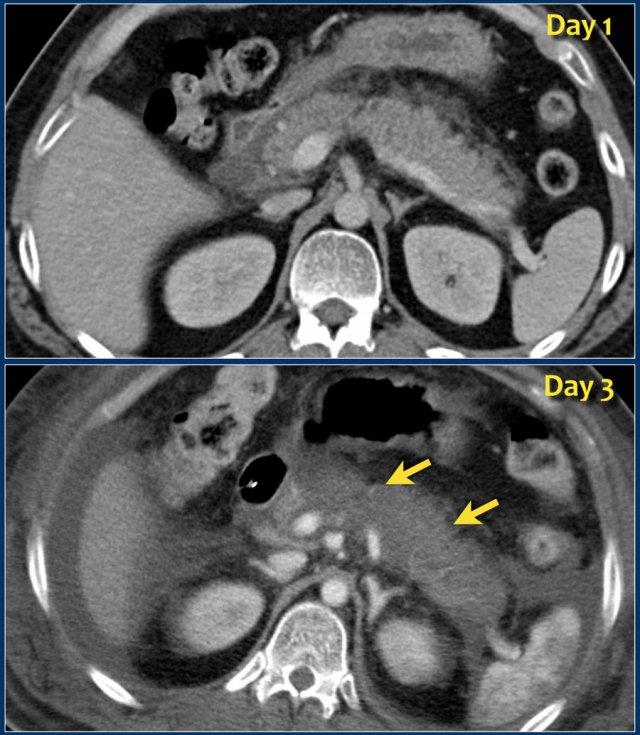

CT thực hiện sớm có thể gây nhận định sai về mức độ nặng về hình thái của viêm tụy, do có thể đánh giá thấp sự hiện diện và mức độ hoại tử.

Các hình ảnh cho thấy tụy ngấm thuốc bình thường vào ngày thứ 1.

Khi tình trạng bệnh nhân xấu đi, CT lần hai được thực hiện vào ngày thứ 3.

Lưu ý phần lớn thân và đuôi tụy không còn ngấm thuốc, gợi ý viêm tụy hoại tử (các mũi tên).

CT lần đầu đã đánh giá thấp mức độ nặng của viêm tụy.

Bệnh nhân này tử vong vào ngày thứ 5 do hội chứng đáp ứng viêm hệ thống (SIRS) nặng và suy đa tạng.